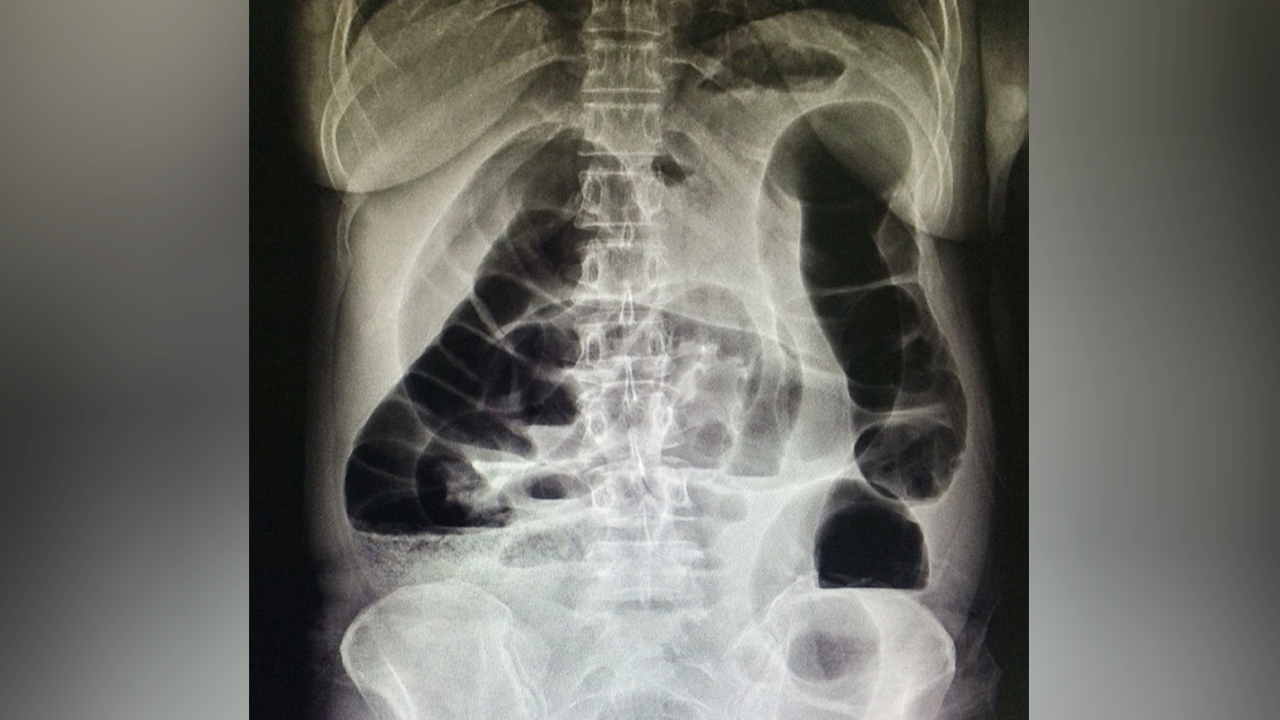

หมออารักษ์ เล่าเคสคนไข้วัย 68 ปี ท้องผูกเรื้อรัง กินยาระบาย สวนสบู่เป็นประจำ สุดท้ายลำไส้อุดตัดต้องผ่าตัดต่อลำไส้ใหม่

วันที่ 18 ส.ค.62 นพ.อารักษ์ วงศ์วรชาติ ผู้อำนวยการโรงพยาบาลสิชล จ.นครศรีธรรมราช โพสต์ภาพและข้อความเตือนภัยกรณีท้องผูกเรื้อรังจนลำไส้อุดตัน โดยยกตัวอย่าง คนไข้อายุ 68 ปี มีอาการท้องผูก 3-4 วันจึงจะขับถ่าย อุจจาระแข็ง กินยาระบาย มีการสวนสบู่เป็นประจำ

จนในที่สุดลำไส้เกิดอุดตัน มีอาการท้องอืด ท้องอืดมาก ต้องเข้ารับการผ่าตัดฉุกเฉินตัดลำไส้บางส่วนที่โป่งพองอย่างมากทิ้งไป แล้วต่อลำไส้ใหม่ "ท้องผูกเรื้อรัง จึงไม่ใช่ภาวะปกติที่ปล่อยวางได้".